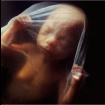

12. týden